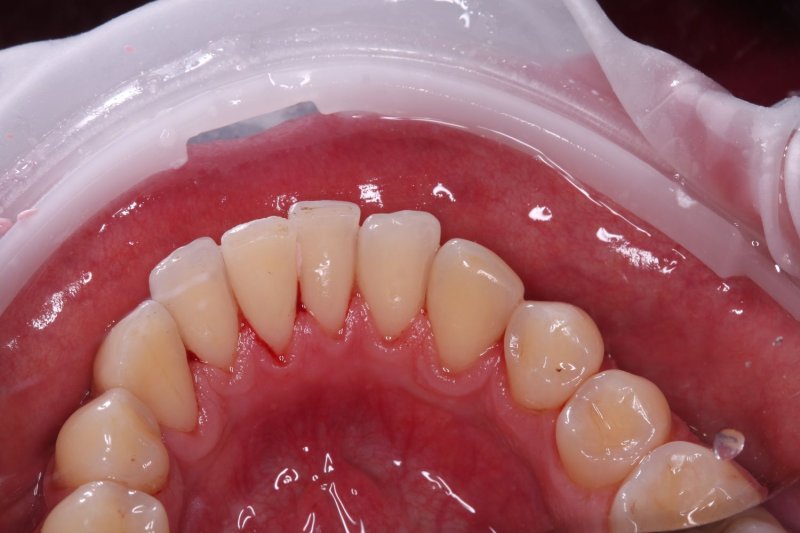

До

udalenie-naleta-ot-kureniya-gbt-do

Наличие мягких и твердых зубных отложений, осложненных стойким эстетическим дефектом — пигментированным налетом от курения и употребления кофе, который не удаляется обычной щеткой.